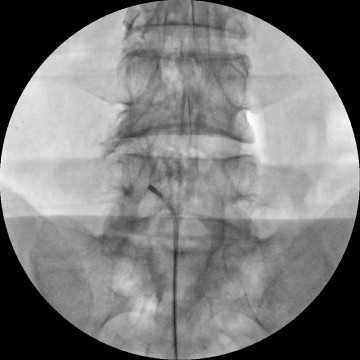

신경성형술

2020.01.21

2020.10.06

2021.02.25